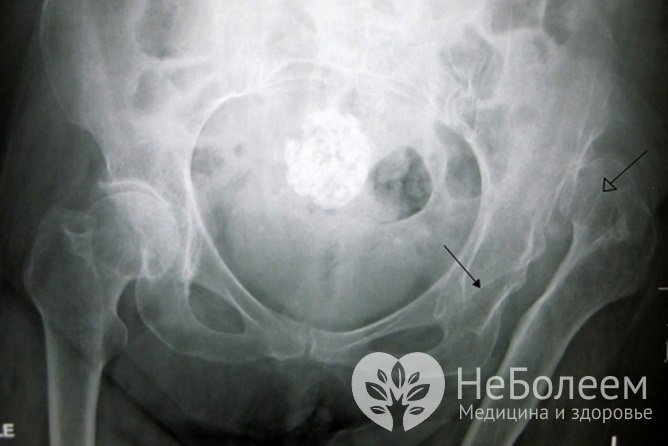

Дисплазия тазобедренного сустава на рентгенографииТерапия дисплазии тазобедренного сустава основывается на придании нижним конечностям вынужденного положения полного отведения в соответствующих суставах с их сгибанием до угла 90º с сохранением активных движений.